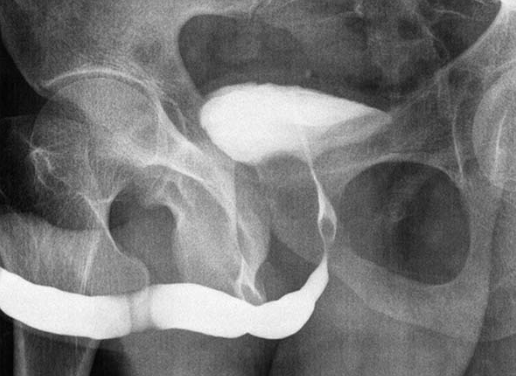

UCM Normal Masculina e Feminina

Comparativo de imagens da fase miccional em um exame normal masculino (esquerda) e feminino (direita).